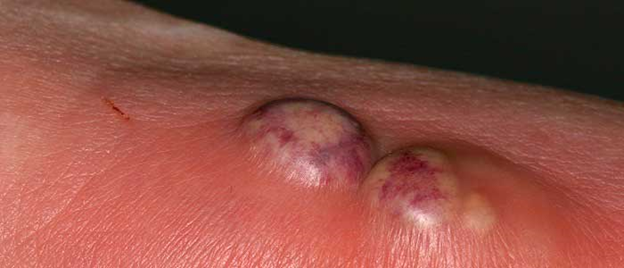

SCABİES (UYUZ)

Uyuz; Sarcoptes scabiei var. Hominis adı verilen akarın (böcek) sebep olduğu tüm dünyada yaygın olarak görülen bir hastalıktır.

Uyuz böceği deride tüneller açarak bu tünellerin içinde yaşar.

İlk defa uyuza yakalanan bir kişide belirtilerin başlaması 2-6 hafta kadar sürebilir. Ancak daha önce uyuza yakalanan bir kişide, belirtiler genellikle maruz kaldıktan 1-4 gün içinde ortaya çıkar. Hastalık belirtilerinin başlamadığı bu dönemlerde bile kişi uyuzu başkalarına bulaştırabilir.

Uyuzun en önemli belirtisi şiddetli gece kaşıntısıdır. Kaşıntı, kişinin yatağa girip ısınması ile artar ve kişiyi uykudan uyandırabilecek şiddette iken gündüzleri daha hafiftir. Kaşıntı genellikle el parmak araları, el bileğinin iç yüzü, bilekler, koltuk altları, dirsekler ve kasıklarda görülmekle birlikte tüm vücutta görülebilmektedir. Hastalığın en belirgin bulgusu parmaklar arasında dalgalı kirli bir çizgi halinde görülen, uyuz böceğinin içinde yaşadığı, gri beyaz renkli, 1-10 mm uzunluğundaki tünellerdir. Kişilerde özellikle geceleri artan şiddetli kaşıntı ve deride görülen içi su dolu keseciklerin görülmesi uyuz şüphesini arttırır.

CloseSCABİES (UYUZ)

Uyuz; Sarcoptes scabiei var. Hominis adı verilen akarın (böcek) sebep olduğu tüm dünyada yaygın olarak görülen bir hastalıktır.

Uyuz böceği deride tüneller açarak bu tünellerin içinde yaşar.

İlk defa uyuza yakalanan bir kişide belirtilerin başlaması 2-6 hafta kadar sürebilir. Ancak daha önce uyuza yakalanan bir kişide, belirtiler genellikle maruz kaldıktan 1-4 gün içinde ortaya çıkar. Hastalık belirtilerinin başlamadığı bu dönemlerde bile kişi uyuzu başkalarına bulaştırabilir.Uyuzun en önemli belirtisi şiddetli gece kaşıntısıdır. Kaşıntı, kişinin yatağa girip ısınması ile artar ve kişiyi uykudan uyandırabilecek şiddette iken gündüzleri daha hafiftir. Kaşıntı genellikle el parmak araları, el bileğinin iç yüzü, bilekler, koltuk altları, dirsekler ve kasıklarda görülmekle birlikte tüm vücutta görülebilmektedir. Hastalığın en belirgin bulgusu parmaklar arasında dalgalı kirli bir çizgi halinde görülen, uyuz böceğinin içinde yaşadığı, gri beyaz renkli, 1-10 mm uzunluğundaki tünellerdir. Kişilerde özellikle geceleri artan şiddetli kaşıntı ve deride görülen içi su dolu keseciklerin görülmesi uyuz şüphesini arttırır.